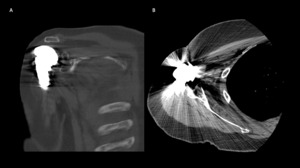

A 69-year-old woman presented after resection arthroplasty of her right shoulder hemiarthroplasty and completion of antibiotic treatment for culture negative PJI for evaluation of reconstructive options. She had a history of a displaced two-part right proximal humeral fracture which was repaired with an intramedullary nail. Post operatively, she had persistent pain and CT scan of the shoulder showed two screws in the humeral head that extended through the cortex and into the glenohumeral joint. The screws were removed and replaced with smaller screws. Subsequently, she had non-union of the fracture in the setting of deltoid weakness and was revised to a right hemiarthroplasty (Figures 1-3). Post operatively, she had persistent pain refractory to physical therapy and diminished function that was impacting her quality of life. She sought subsequent care, and there was concern for arthroplasty failure secondary to a septic versus aseptic condition and the decision to proceed with resection arthroplasty was made. During resection arthroplasty, a significant amount of fluid was expressed from the joint space. The combination of the clinical picture of progressive and persistent pain and the gross expression of fluid were concerning for PJI and the decision to treat was made. It was felt that the extent of humeral bone loss did not allow for a stable cement spacer, so none was placed. Intraoperative joint fluid cultures, anaerobic, and fungal cultures were all negative for growth. Cultures were held for 21 days to rule out C. Acnes infection. Considering the plan for future reimplantation, infectious disease consultation recommended a 6-week course of vancomycin but after 2 days the patient had a transfusion reaction and was switched to daptomycin. She was left with markedly limited active motion associated with severe pain. After completion of the antibiotic course, the patient elected to proceed with revision surgery. This patient had a flattened and distorted glenoid and atrophied rotator cuff musculature demonstrated prior to resection arthroplasty on CT (Figure 4). This patient’s prior hemiarthroplasty had been a tantalum coated, cemented humeral stem with associated marked thinning of the humeral cortex even prior to resection arthroplasty, and this resulted in a large amount of proximal humeral bone loss during the resection (Figure 5). The patient was severely debilitated by the right shoulder and wanted to proceed with reconstruction. Because of the combination of glenoid and humeral bone loss and the lack of rotator cuff attachments, a custom constrained prosthesis design process was initiated, and the implant was available 16 months after the resection arthroplasty. Preoperative 3 phase SPECT (Single Photon Emission Computed Tomography) three phase bone scan, upper extremity CT, and blood work (WBC 5.4, ESR 9, CRP 0.8) showed no suggestion of active infection.